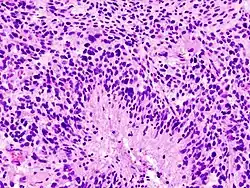

Obraz histologiczny

Histologicznie stwierdza się bardzo dużą atypię komórek i obecność ognisk martwicy otoczonych gęstym pasem komórek nowotworowych – tzw. martwica palisadowata. Ogniskowo proliferują drobne naczynia.